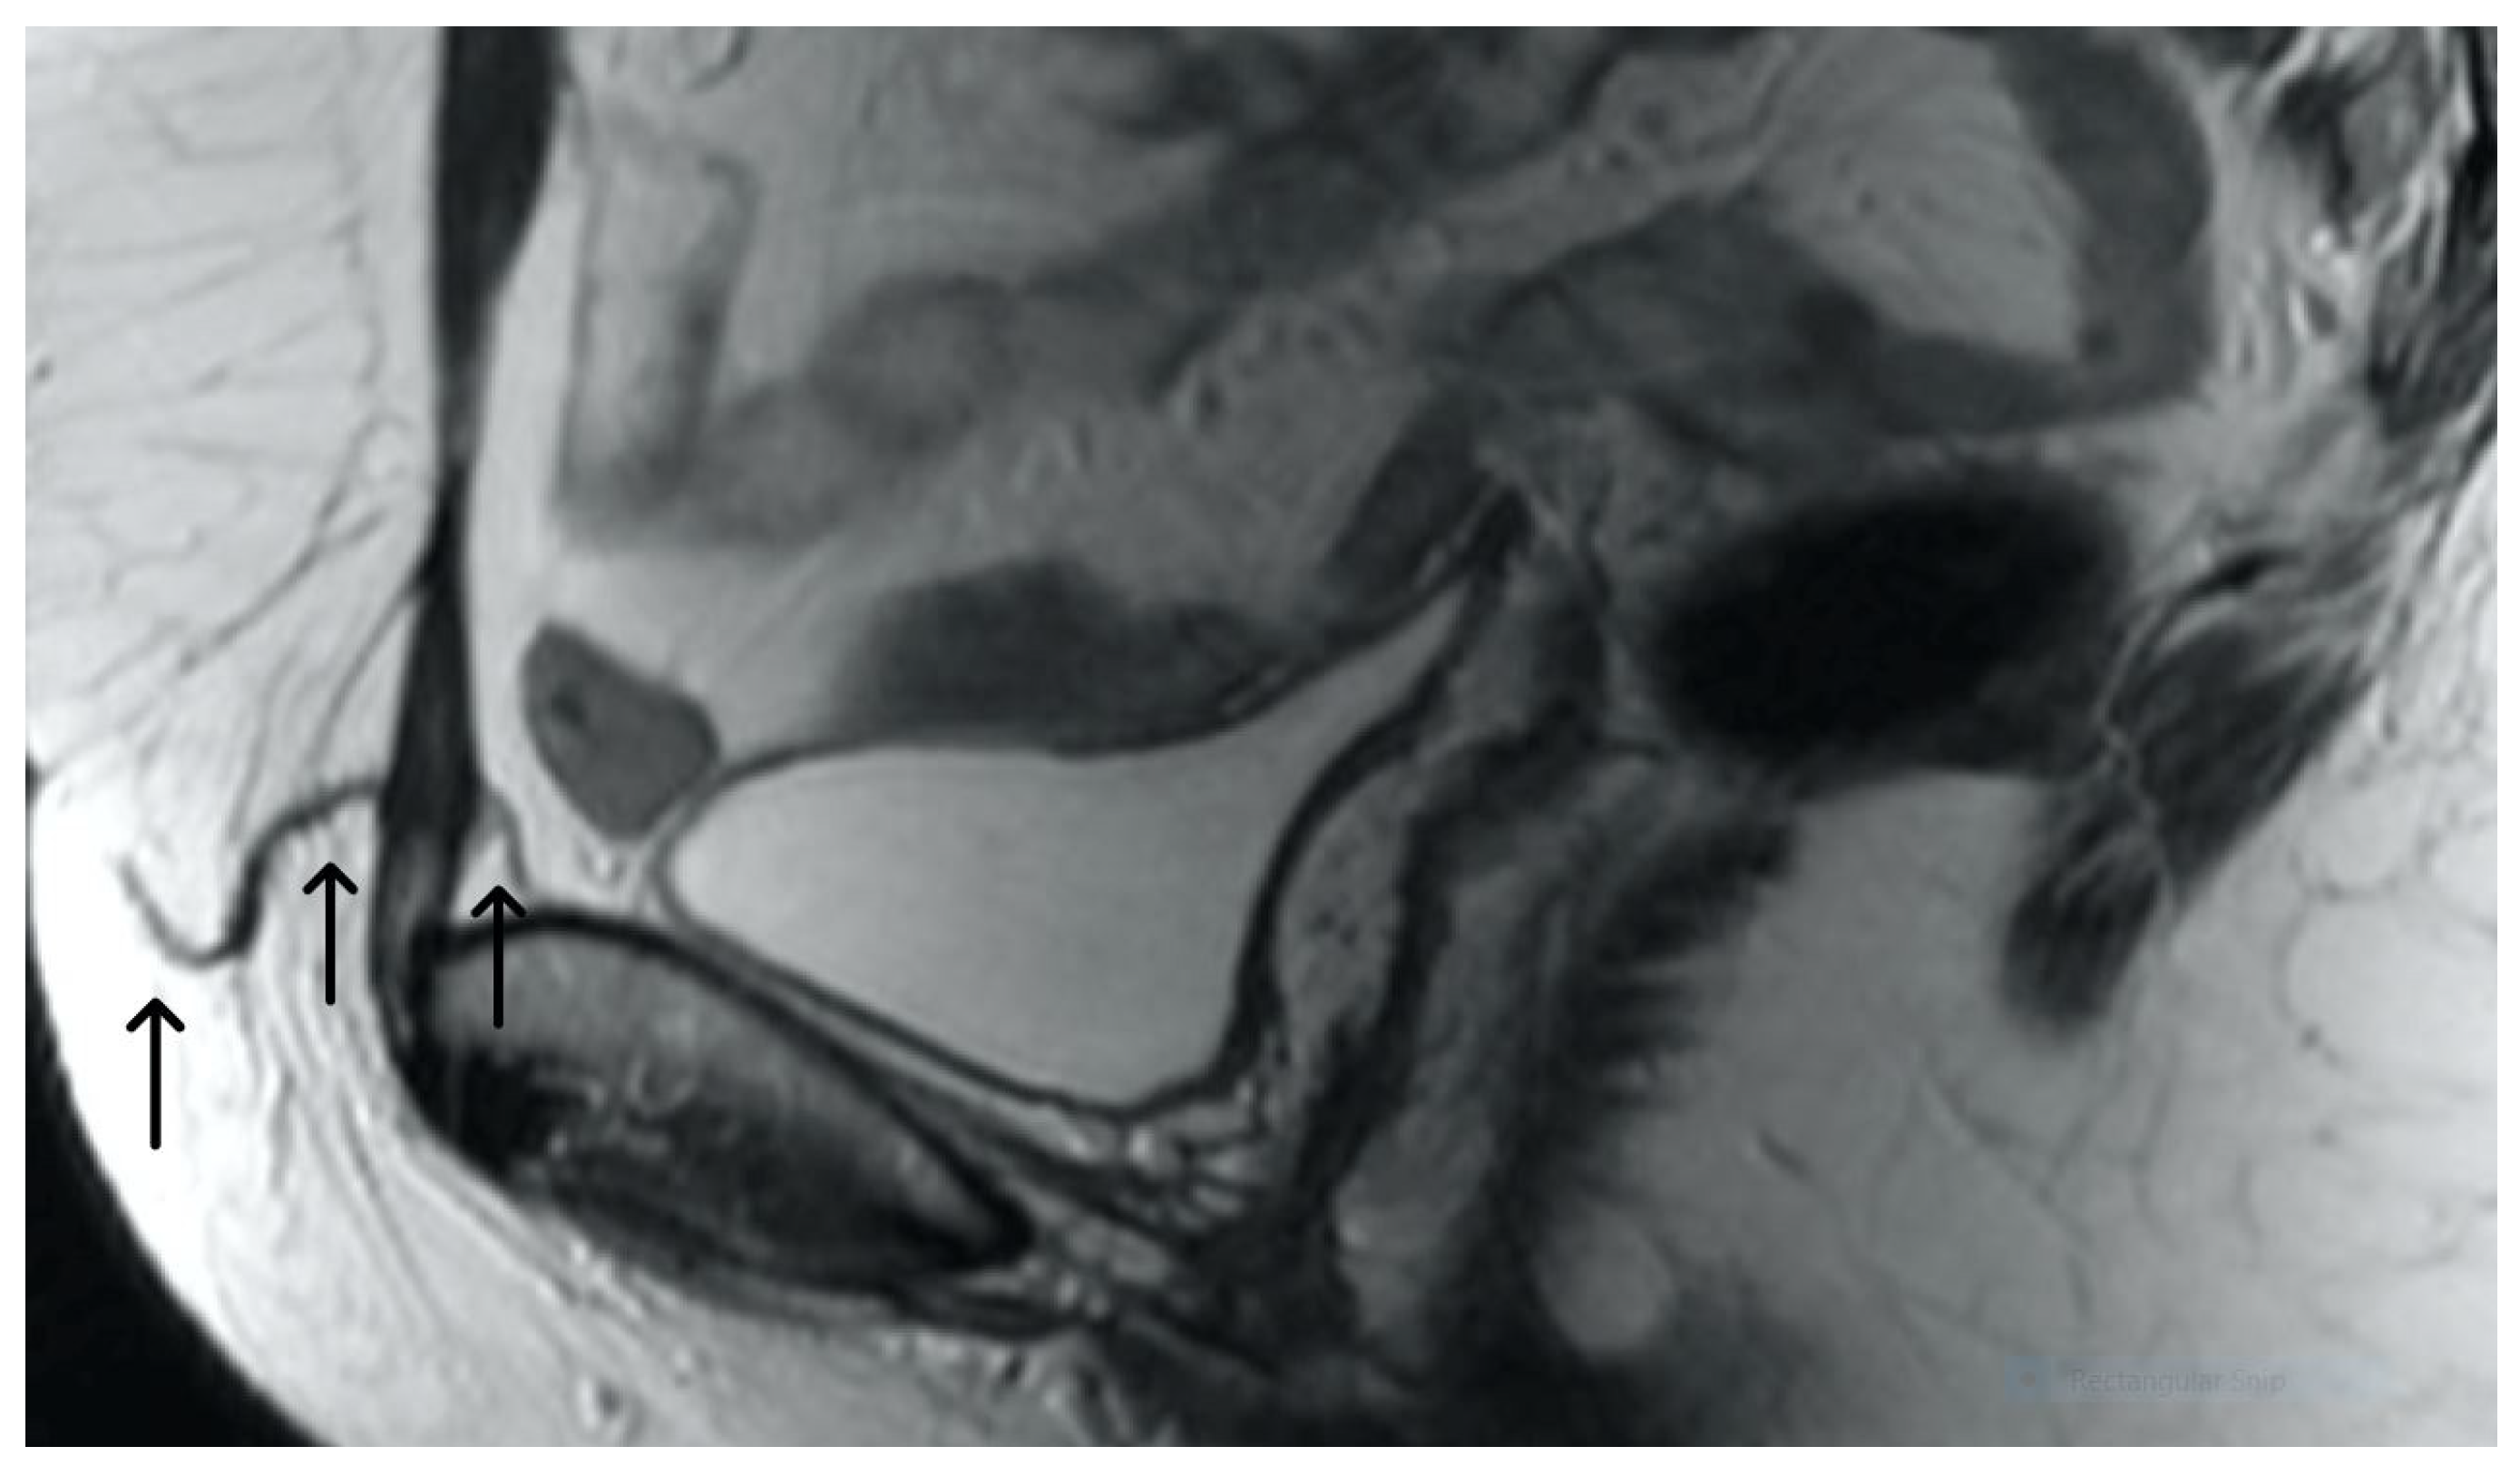

3. Normal Appearance of Urethral Meshes on MRI/CT